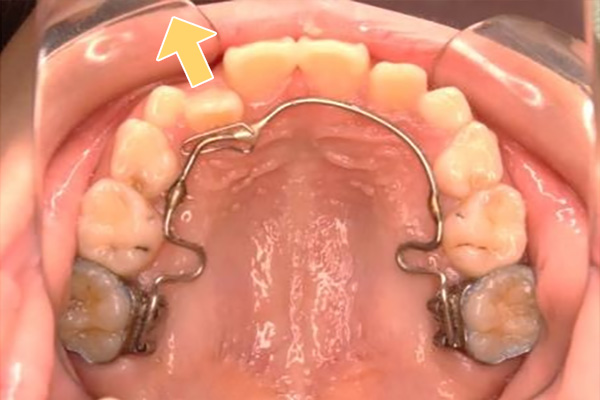

また、特定の症例では、写真にあるような固定式装置を併用する場合もございます。固定式装置はお口の中に常時存在するため、歯磨きのしにくさや舌の癖を引き起こす可能性があり、必要最小限の使用にとどめています。